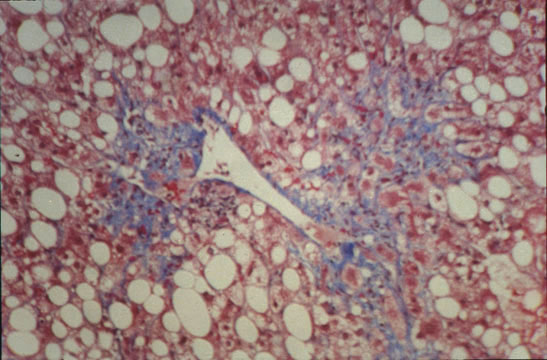

Central fibrosis, severe

Fig.67 - CENTRAL FIBROSIS, SEVERE: This form of fibrosis mostly occuring in alcoholics goes under the name of "sclerosing hyalin necrosis". It consists of wide pericentral areas of fibrosis that may extend to portal fields.